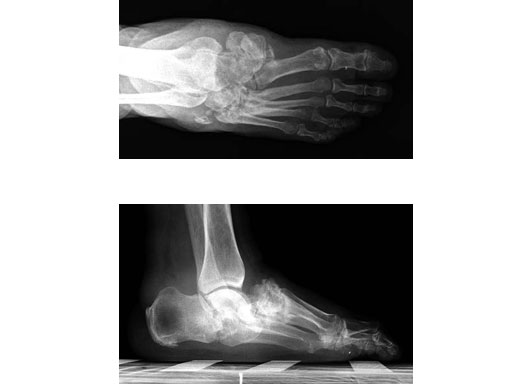

Case 1: 47-year-old female

Case provided by Andrew K Sands, New York, USA

Charcot foot treated with MFB and X-plate